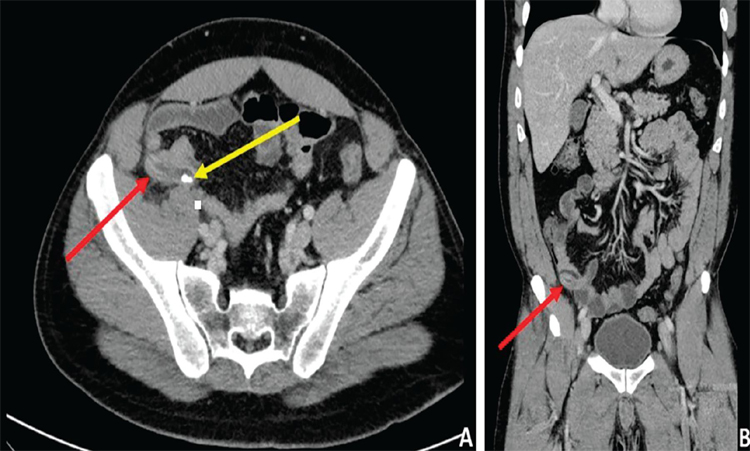

سی تی اسکن اسپیرال در بسیاری از زمینههای پزشکی کاربرد دارد. یکی از مهمترین کاربردها، تشخیص بیماریهای گوارشی است. این روش میتواند به شناسایی مشکلاتی مانند آپاندیسیت، تومورهای روده و بیماریهای التهابی روده کمک کند. همچنین، سی تی اسکن اسپیرال میتواند در ارزیابی عوارض پس از جراحیهای شکمی و لگنی نیز مؤثر باشد و به پزشکان در برنامهریزی برای درمانهای بعدی یاری رساند.

در مقایسه با روشهای سنتی که تنها تصاویری دو بعدی تولید میکنند، سی تی اسکن اسپیرال با چرخش تیوب اشعه ایکس به دور بیمار، امکان تولید تصاویری سهبعدی را فراهم میکند. این ویژگی به پزشکان این امکان را میدهد که ساختارهای داخلی بدن را به دقت بررسی کنند و در نتیجه تشخیصهای دقیقتری انجام دهند. این روش به ویژه در بررسی نواحی شکم و لگن که شامل اندامهای حساسی مانند روده، کبد و مثانه است، بسیار مؤثر است.

همچنین، سی تی اسکن اسپیرال میتواند با استفاده از مواد کنتراست، تصاویری با وضوح بالاتر تولید کند. این مواد معمولاً به صورت مایع یا گاز به بیمار تزریق یا بلعیده میشوند و به پزشکان کمک میکنند تا ساختارهای داخلی را بهتر مشاهده کنند. استفاده از این مواد کنتراست به ویژه در تشخیص بیماریهایی مانند تومورها، عفونتها و اختلالات عروقی اهمیت دارد و میتواند به بهبود دقت تشخیص کمک کند.